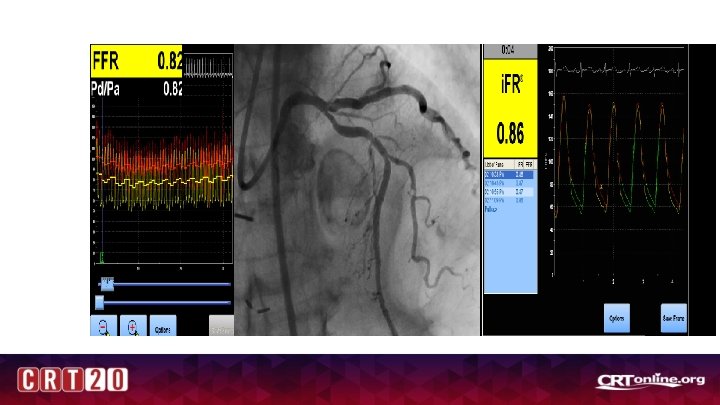

Where is the culprit?

Unclear Culprit

i. FR

Conclusions • Event rate is higher in deferred lesions in NSTEMI /ACS patients • Non-culprit vessel FFR is reliable and did not change significantly at follow up (although only at ~1 month- 6 month may be different) • Culprit vessel –FFR reliable and better than Angio-guided, but may be falsely negative in patients with high troponins and CRP and higher LVEDP (20 -25% of patients) -Also trend towards more events , spontaneous MI at follow up • IFR vs FFR data is ACS is interesting and needs further study • Co-Registration with resting indices may have promise in unclear culprit subsets